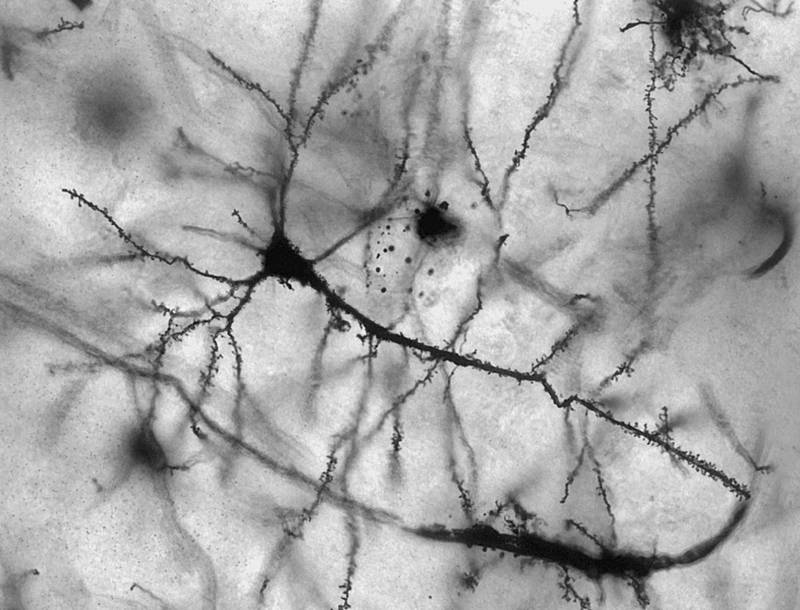

Разрушить эту устоявшуюся истину более ста лет назад, в 1906 году, попытался известный испанский гистолог и нобелевский лауреат Сантьяго Рамон-и-Кахаль. Однако «новорожденных» нейронов в головном мозге человека он не нашел.

Ради справедливости следует отметить, что еще в 1956 году российский биолог И. Рампан восстановление нервной ткани обнаружил у собак, волков, а также крыс и других видов животных. Он выяснил, что после повреждения мозга сохранившиеся нервные клетки светлеют и внутри них формируются два ядра, затем делится пополам цитоплазма. В результате этого процесса появляются два нейрона, то есть новые нервные клетки.

Затем, с разницей в несколько лет, в 1962 году американский ученый Жозеф Олтман провел эксперимент, который доказывал наличие у млекопитающих нейрогенеза – возникновения новых нервных клеток в головном мозге взрослых животных. Для этого ученый с помощью электрического тока разрушил один из участков мозга крысы и ввел в него радиоактивное вещество, обладающее способностью проникать в молодые клетки. А спустя несколько месяцев Олтман обнаружил новые радиоактивные нейроны в таламусе и коре головного мозга.

И, действительно, спустя всего несколько часов после введения препарата в мозге животных обнаружились новые нейроны. Было также установлено и место, где они рождались. Им оказался гиппокамп – отдел мозга, играющий ведущую роль в формировании памяти.

Получив разрешение на исследование головного мозга пациентов, умерших от рака, ученый в конце 1998 года обнародовал сенсационный результат: в гиппокампе больных людей каждый день вплоть до их смерти возникало от пятисот до тысячи нейронов.